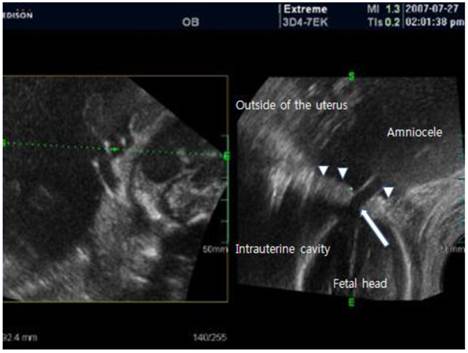

Fig 1

3D transabdominal ultrasound finding. About 15 X 15cm sized large cystic mass was noted outside of the uterus. The cyst was an amniotic sac protruding through the ruptured site of the uterus; below the site, the fetal head was seen in the uterus cavity. arrow: ruptured site of the uterus; arrow head: intact uterus wall.

A 30-year-old patient, with a history of 2 vaginal deliveries and amniocentesis 1 week prior to admission, was referred at 23 weeks gestation for evaluation of a large abdominal cyst and abdominal discomfort. Abdominal discomfort occurred 2 days before visit, and was aggravated on the day of visit. The patient was a non-smoker and had no underlying diseases. She had not consumed alcohol during her pregnancy. On examination, the abdomen was tender; the abdomen protruded more than the right side than on the left side. Her blood pressure was 120/70 mmHg; heart rate 100 beats/min and body temperature, 36.8℃. We performed transabdominal and transvaginal 2D ultrasound; a large cystic mass was noted on her left adnexa area and oligohydramnios with intrauterine fetus was noted. The cervix was closed and measured 4 cm in length. Three-dimensional (3D) ultrasound (ACCUVIX, Medison, Seoul) was performed and we noted that the umbilical cord had herniated through uterus wall and about 15 X 15 cm sized large amniotic sac had herniated through the uterine wall, 3D image suspected uterine ruptured part (2 cm) of the uterus on the left fundal uterine wall (Fig. 1 and Fig. 2). Laboratory analysis showed a hemoglobin level of 11.3g/dL, a white blood cell count of 15350 cells/mm3 and a C-reactive protein of 1.34 mg/dL. During the hospital observation period (5 hours), the patient complained of vaginal bleeding and progressive lower abdominal pain. Five hours later, the patient's abdominal pain and vaginal bleeding worsened; the blood pressure dropped to 100/80 mmHg and the pulse was 120 beats/min. The treatment team decided to proceed with exploratory laparotomy under general anesthesia. During the procedure and upon entering the abdominal cavity, the entire amniotic sac containing the fetus protruded through a 4 cm ruptured left fundal uterine wall and about 1000 mL hemoperitoneum was detected (Fig. 3). The fetus was delivery by Cesarean section using a classic uterine incision. The fetus expired (male, 700 g) immediately after delivery. Amniotic fluid was clear and not odorful. After removal of the placenta, a double layer of 2-0 chromic was used to close the uterine defect. The patient was discharged 5 days later.

There is little doubt that prompt recognition of uterine rupture and expeditious recourse to laparotomy remain the critical factors influencing morbidity and mortality of the mother and of the fetus. An amniocele is a herniation of the amniotic sac through a uterine defect [7]. Our case was initially diagnosed as a large abdominal cystic mass, but after 3D-ultrasound assisted identification of the uterine rupture, and by finding amniocele connected to the defect, we ensured an accurate diagnosis. The diagnosis could have been possible using 2D ultrasound by close observation, but with 3D ultrasound, 3-dimensional observation on the uterine defect was more helpful towards making a definite diagnosis. In addition, when the defect was located at the posterior of uterus where it was difficult to make an observation with 2D ultrasound, 3D ultrasound had superior values to 2D ultrasound. Since antepartum uterine rupture is a life threatening event to the mother and fetus, a rapid and accurate diagnosis is very important to improve prognosis.